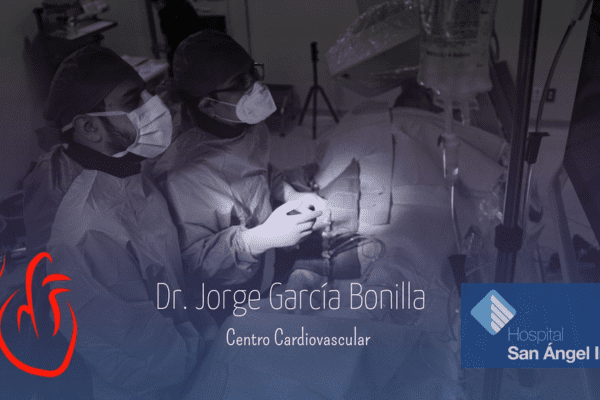

Conoce mis instalaciones y algunos casos de pacientes en mi